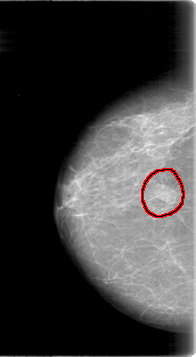

D_4015_1.RIGHT_CC

RIGHT_CC LINES 5341 PIXELS_PER_LINE 2926 BITS_PER_PIXEL 12 RESOLUTION 43.5 OVERLAY

FILE: D_4015_1.RIGHT_CC.OVERLAY

TOTAL_ABNORMALITIES 1

ABNORMALITY 1

LESION_TYPE MASS SHAPE OVAL MARGINS OBSCURED

ASSESSMENT 0

SUBTLETY 4

PATHOLOGY BENIGN

TOTAL_OUTLINES 1

BOUNDARY